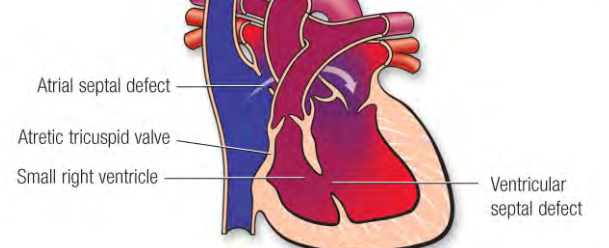

Atresie de la Valve tricuspide

- Bord graisseux et musculaire en lieu et place de la valve tricuspide

- VD hypoplasique

- CIV et CIA